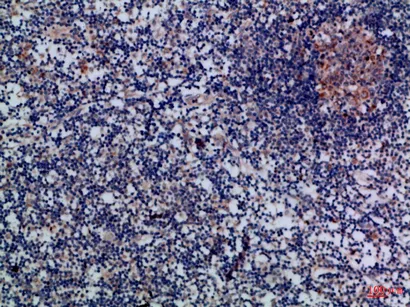

Granzyme M Rabbit Polyclonal Antibody

Cat: APRab11744

Size1:50μl Price1:$118

Size2:100μl Price2:$220

Size3:500μl Price3:$980